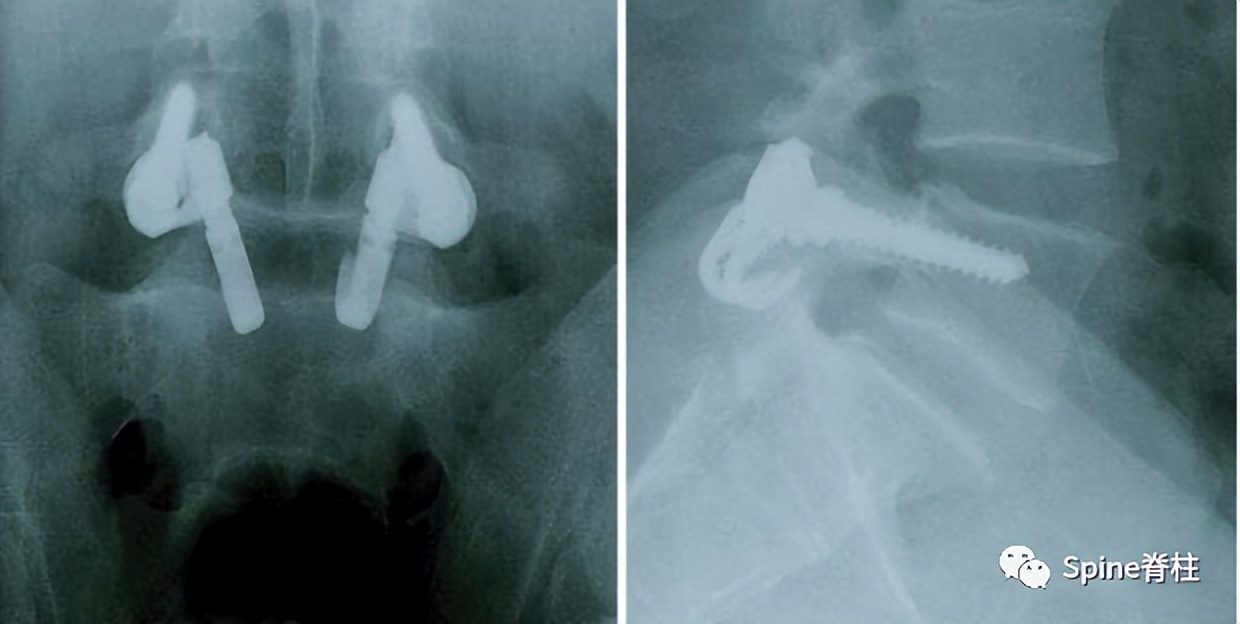

1. 椎弓根螺钉-钉钩系统

PMID: 9199377

PMID: 15699811

PMID: 17520298